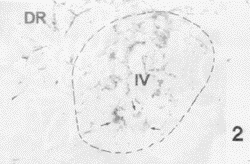

图2 滑车神经核(Ⅳ)内中等密度的SP受体样阳性纤维和弱阳性神经元(箭头)。DR.中缝背核

Fig.2 Middle density SPR-LI fibers and weakly stained SPR-LI neurons (arrows) in the trochlear nucleus (Ⅳ). DR:dorsal raphe nucleus.